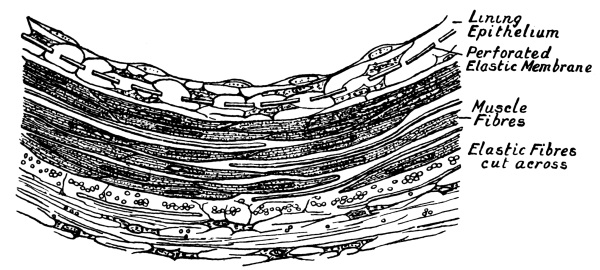

| 12. | Section of the Wall of a Small Artery | 233 |